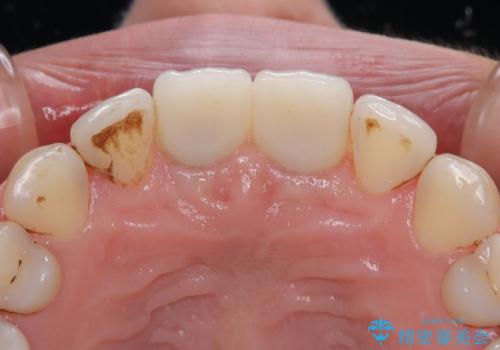

初めは前歯のみの処置で改善を希望されていたため、広範囲に処置範囲を広げることで歯の幅がバランスする治療を提案しましたが、削らなければならない歯が増えてしまうため、患者様と相談して全顎矯正により前歯のスペースを閉じていくこととしました。

不適合なクラウンが装着されていたため、歯周ポケットが深くなっていましたので、矯正治療前に歯周外科処置を行って歯周ポケットを除去し、矯正治療後にオールセラミッククラウンにて補綴治療を行うこととしました。

前歯の見た目はもちろん、出血や腫脹のない健全な前歯の状態を獲得することができました。